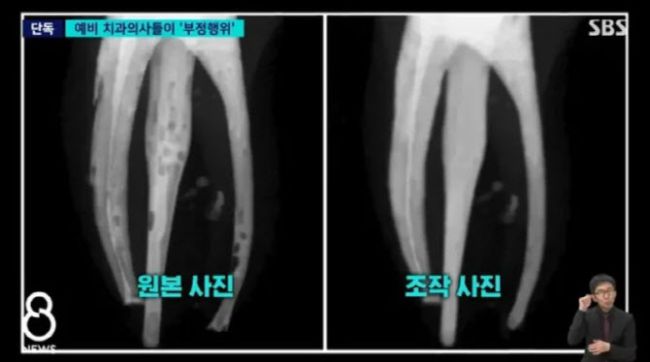

연세대 치과대학 학생들이 집단 부정행위를 저질러 징계받은 사실이 알려졌다. 연세대는 지난해 2학기에도 한 교양과목서 집단 부정행위가 연이어 발각돼 파문이 일었다. 제대로 치료가 안 된 원본사진(왼쪽)과 포토샵으로 조작해 교수에 제출한 사진이다. (사진=SBS 캡처) 13일 SBS에 따르면 지난해 2학기 연세대 치대 ‘신경치료 실습’ 수업을 수강한 본과 4학